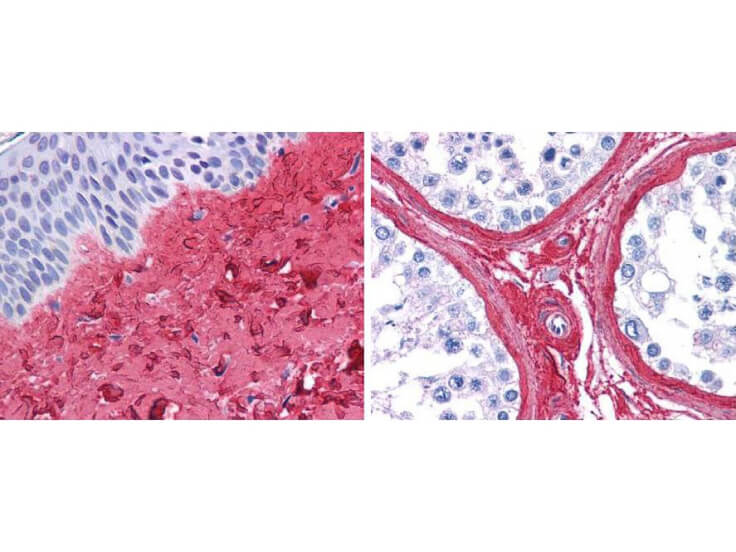

Collagens are a family of fibrillar proteins forming the structural framework of connective tissues such as skin, tendons, joints, and bones. Renowned for their exceptional strength and high elasticity, collagen fibers play a crucial role in maintaining the integrity of connective tissue. In cell culture, collagen is frequently used to mimic the natural extracellular matrix, creating an environment that supports cell attachment and growth. Additionally, collagen is a primary component in many cosmetic formulations due to its moisturizing, regenerating, and film-forming properties. Rockland supports research with a variety of collagen products, including highly cited collagen antibodies, purified collagen proteins, collagen-coated flasks and plates, and raw materials for collagen extraction. Rockland also offers supporting services such as custom antibody production, solutions for impurity detection, and protein expression and purification services.

Collagen antibodies are vital tools in research and diagnostics, used to detect and quantify collagen proteins in various samples. They are essential in studying collagen-related diseases and in the development of collagen-based assays.